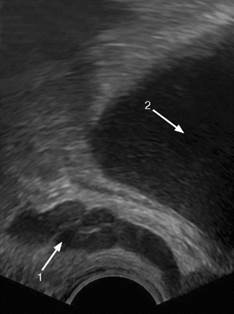

Рис. 4.11. Сонограмма. Солитарная киста почки: 1 - нормальная почечная ткань; 2 – киста

Характер очаговой патологии почки определяется сонографической картиной выявленных изменений - от анэхогенного образования с дорсальным усилением до гиперэхогеннего образования, дающего акустическую тень. Анэхогенное жидкостное образование в проекции почки по своему происхождению может быть кистой (рис. 4.11) или расширением чашечек и лоханки – гидронефрозом (рис. 4.12).